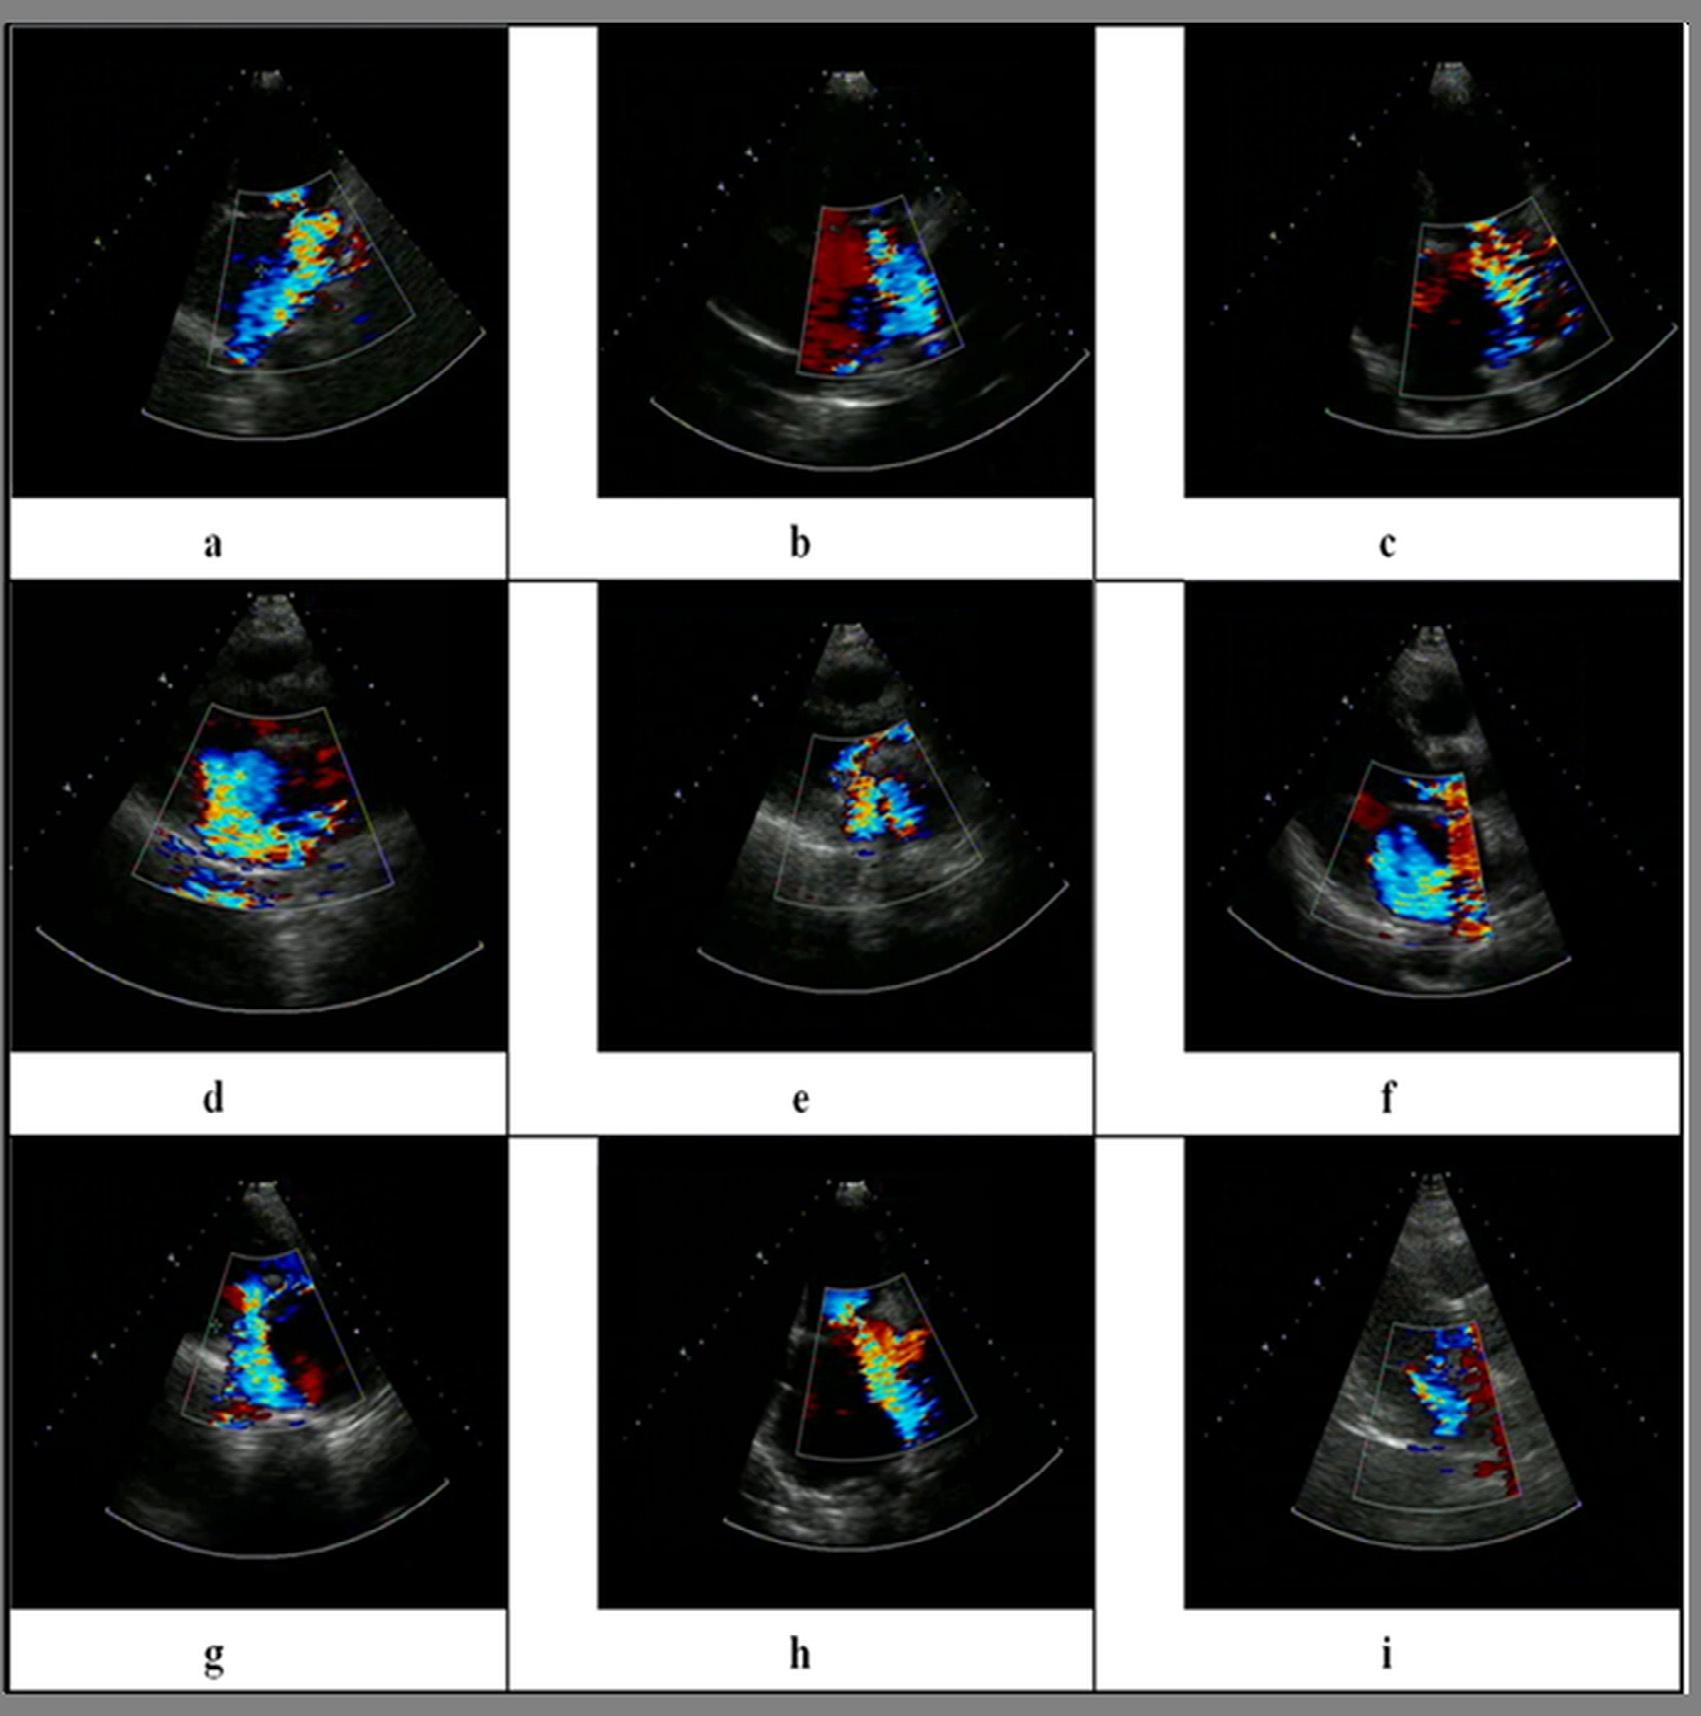

ExampleofcolorDopplerimaginginsystolicparasternallong-axisviewMR.

Fig.1.8 showsa2DimageofbloodflowintotheLAatthetimeofsystoleduringMR [25–31].The colors(redandblue)representthedirectionofagivencolorjetandthedifferentvelocities,whichcan berepresentedbyhuesfromdulltobright.Aturbulentjetshowsthemosaicpatternofmanycolors.A 2Ddisplayofflowisshownaccordingtosize,direction,andvelocity.

Meaningofcolor Thereisusefulinformationintheflowmapofanimage.Thecolorredisassigned totheflowtowardthetransducersandthecolorblueisassignedtotheflowawayfromthetransducers.

Fig.1.10 showsninecasesofMRimagedwithcolorDopplerechocardiography.Theimagesaretaken atdifferentviewsoftheheart.Themosaicpatternofcolorshowstheregurgitation. Inthenextsection,wepresentananalysisofMRfindingsbasedonregurgitantareaandvena contractawidth.

ImagesfromMR-affectedpatientstakenwithcolorDopplerechocardiography [25]